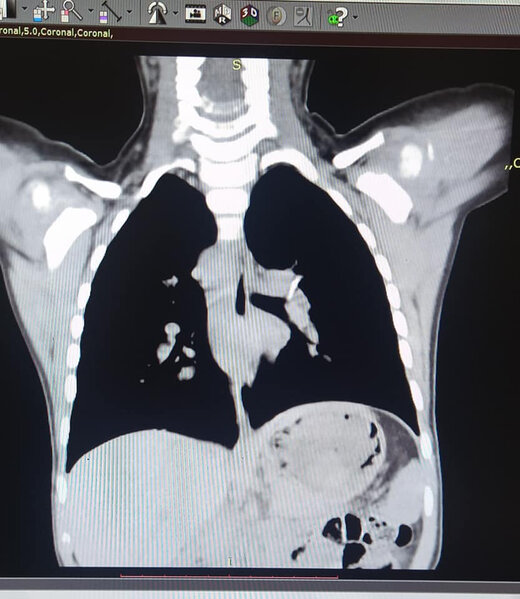

Bakıda 2 yaşlı uşaq bir il nəfəs borusunda sümük parçası ilə yaşayıb - FOTO

İki yaşlı uşaq 1 il nəfəs borusunda sümük parçası ilə yaşayıb.

"Artıq çətinliklə nəfəs alırdı, xırıltı uzaqdan eşidilirdi. Uşağın 1 yaşı olanda balıq yediyini deyirlər və ondan sonra qızdırma öskürək, xırıltı başlayıb. Aparılan bütün müalicələrə baxmayaraq xırıltı, öskürək getdikcə artırdı və tez-tez temperaturu yüksəlirdi. Valideynləri vəziyyətinin getdikcə pisləşdiyini və vəziyyətinin ağırlığı ilə əlaqədar müraciət etdikləri klinikalarda qəbul etmədikləri üçün bizim klinikaya müraciət etdilər. Ciddi risk daşısa da uşağın rahat nəfəs alması üçün sümüyü nəfəs borusundan çıxarmaq məcburiyyətində idik. Bronxoskopiya işıqlı alətlə nəfəs borusuna girilərək çətinliklə olsa da sol ana bronxdan sümüyü problemsiz çıxartdıq", - deyə həkim bildirib.